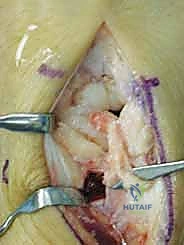

4. يتم تنظيف العظم الهلالي الميت وتفريغه من الأنسجة الميتة (Core Decompression).

5. يُزرع الطعم العظمي الحي (الوعائي) داخل التجويف الذي تم إنشاؤه في العظم الهلالي.

6. تعمل الأوعية الدموية المنقولة كـ "شريان حياة" جديد، حيث تبدأ في تغذية العظم الهلالي، مما يحفز الخلايا العظمية (Osteoblasts) على بناء نسيج عظمي جديد وقوي.

1. يقوم الدكتور هطيف بإجراء قطع عظمي دقيق (Osteotomy) في العظم الكبير.

2. يتم إزالة شريحة صغيرة جداً من العظم (عادة بضعة مليمترات فقط).

3. يتم إعادة تثبيت العظم الكبير باستخدام مسامير دقيقة (Screws) أو دبابيس معدنية (K-wires).